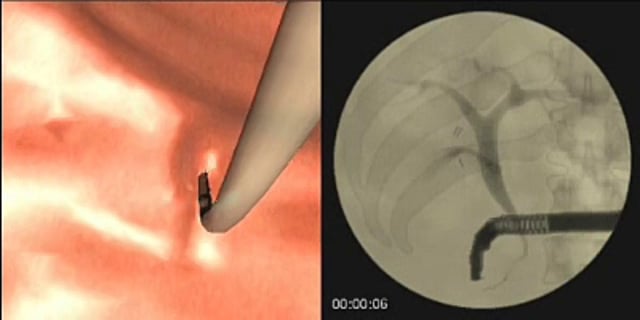

ENDOSCOPIC RETROGRADE CHOLANGIOPANCREATOGRAPHY (ERCP) MODULE

The ERCP modules provide advanced hands-on training for complete procedures of diagnostic and therapeutic ERCP. The cases present with varied anatomies and abnormalities of the biliary tract and/or the pancreatic duct. Learners have the opportunity to practice multiple virtual patient cases with varying anatomies and pathologies of both the common bile duct and the pancreatic duct. The module comes only with GI Mentor on ENDO Suite platform.

Cannulation and Sphincterotomy